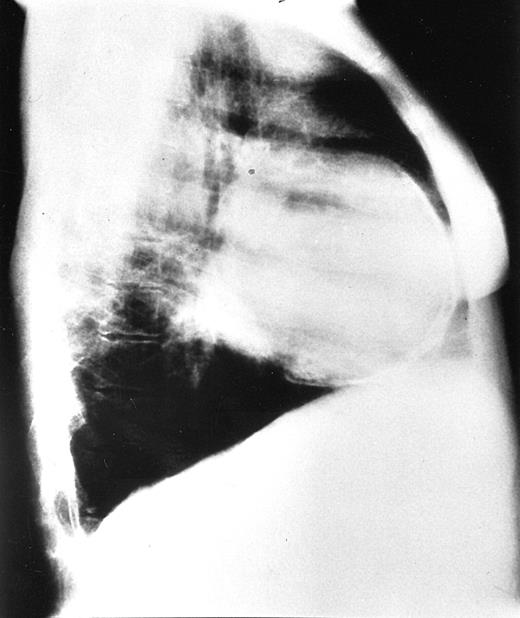

Chest radiographs revealed increased cardiothoracic index levels in 54 (49%) patients. Eighteen (16.3%) had prominent pulmonary arteries. Signs of obvious bone marrow expansion were present in 25 (22.7%) patients and included intrathoracic extramedullary hemopoietic masses in 21 (19%) patients and widening of ribs in 10 (9%) patients (Figure 1). Pericardial calcification was found in a 42-year-old patient with a history of pericarditis but no history of tuberculosis and negative findings on the Mantoux test (Figure 2).

Chest radiograph of the oldest patient with congestive heart failure.

Frontal view (upper panel). Lateral view (lower panel). Patient shows signs of pulmonary hypertension combined with large intrathoracic extramedullary hemopoietic masses.